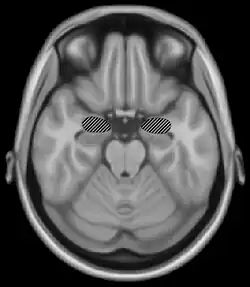

The right secondary auditory cortex has finer pitch resolution than the left. Hyde, Peretz and Zatorre (2008) used functional magnetic resonance imaging (fMRI) in their study to test the involvement of right and left auditory cortical regions in the frequency processing of melodic sequences.[9] As well as finding superior pitch resolution in the right secondary auditory cortex, specific areas found to be involved were the planum temporale (PT) in the secondary auditory cortex, and the primary auditory cortex in the medial section of Heschl's gyrus (HG).

Many neuroimaging studies have found evidence of the importance of right secondary auditory regions in aspects of musical pitch processing, such as melody.[10] Many of these studies such as one by Patterson, Uppenkamp, Johnsrude and Griffiths (2002) also find evidence of a hierarchy of pitch processing. Patterson et al. (2002) used spectrally matched sounds which produced: no pitch, fixed pitch or melody in an fMRI study and found that all conditions activated HG and PT. Sounds with pitch activated more of these regions than sounds without. When a melody was produced activation spread to the superior temporal gyrus (STG) and planum polare (PP). These results support the existence of a pitch processing hierarchy.